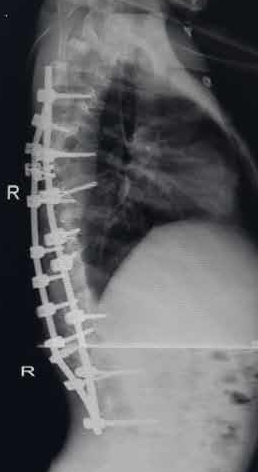

手术由贺西京、李浩鹏教授亲自主刀,并邀请有丰富麻醉经验的李有才教授负责麻醉,在严密的诱发电位全程监护下施行全脊柱截骨矫形术。即将脊椎一节节打断、截骨,再重新排列、固定。因脊柱畸形严重,常规固定方式无法完成,只能凭经验探索进行,并多次进行术中透视,确保矫正角度。如此大范围脊柱矫形,风险极大,术中稍有不慎,无论是术中操作,还是骨片,都有可能损伤血管造成大出血,危及生命。因手术创伤大,时间长,出血多,术中患儿多次出现心率加快、烦燥等症状,通过及时的输血、补充血容量后好转。在完成椎体截骨时,脊髓也要完成近120度的变位,此时极易损伤神经,风险极大。神经损伤会造成患儿终身瘫痪,双下肢丧失运动、感觉功能,并出现大小便失禁等,因此要求术者一定要心细,操作要轻、准。并通过诱发电位,及时反复监测神经传导速度,判定神经功能。在手术、麻醉及护理人员的紧密配合下,经过近10小时紧张、细致的手术,手术取得成功,矫形由患儿颈后部到腰下段的脊柱全段,缝合30余针,术中输血1800毫升,术中矫正脊柱畸形角度约120度。术后患儿即可平卧,背部的罗锅畸形显著改善,双下肢感觉、运动良好,自解小便,身高由术前的130cm增加到142cm。患儿及家属对手术效果非常满意。